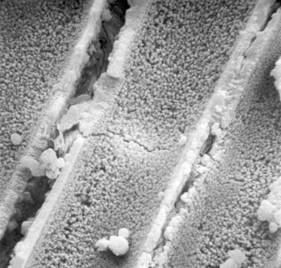

Drobné kulovité agregáty krystalků

apatitu,

diagonální strukturu uvnitř tvoří otisk chirurgického šicího materiálu.

Elektronový mikroskop, zvětšení 2000x